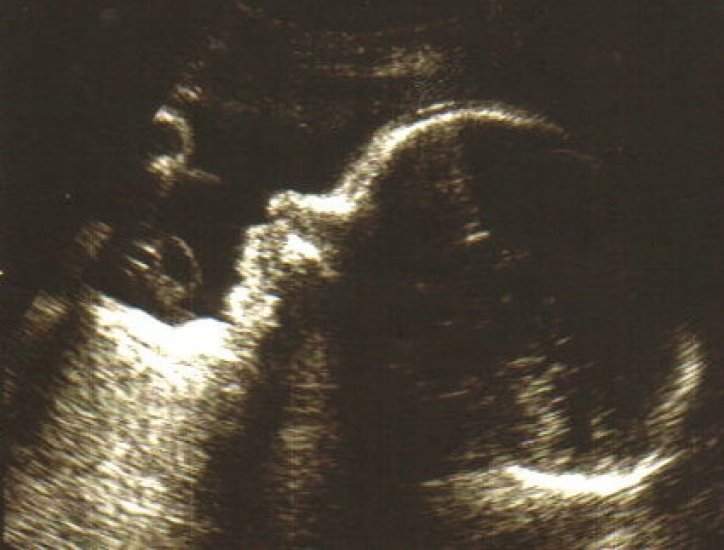

Pregnancy progression underwater week by week Diving underwater during pregnancy YouTube